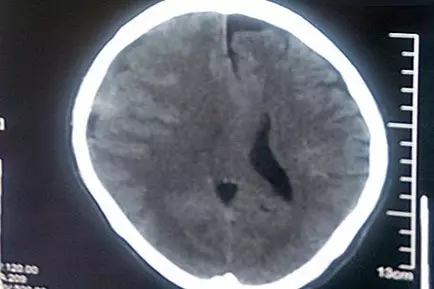

患者術(shù)前CT影像:腦中線結(jié)構(gòu)向左偏移

老馮才告訴了家人。縣醫(yī)院CT診斷結(jié)果比他想象的嚴(yán)重得多!這大樹(shù)枝把他砸出了亞急性硬腦膜下血腫,出血量較大,腦中線已經(jīng)移位,并有腦疝風(fēng)險(xiǎn)。馬不停蹄的老馮一家到了省城的三甲醫(yī)院,接著又趕到了上海的三甲醫(yī)院,然而都以各種理由被建議轉(zhuǎn)院治療。不幸中的萬(wàn)幸是,老馮的亞急性硬腦膜下出血相比急性硬腦膜下出血,出血速度稍緩,所以血腫形成至腦受壓的過(guò)程略長(zhǎng),為老馮四處求醫(yī)爭(zhēng)取了寶貴的時(shí)機(jī)。